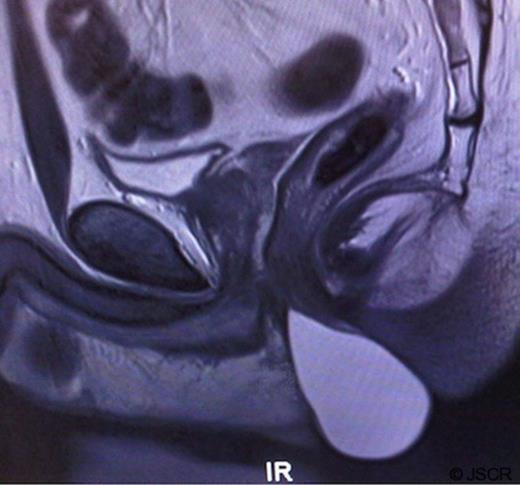

Further characterisation using magnetic resonance imaging (MRI) revealed a very well defined mass returning high signal on T2 weighted images suggesting fluid or proteinaceous contents. The lesion appeared to originate from between the internal and external anal sphincters, with the superior part of the lesion therefore lying in the intersphincteric plane and the lower part bulging out into the perineum. (Figure 1)

MRI of the pelvis showing a large cystic mass arising from the intersphincteric plane, lying anterior to the anal canal.